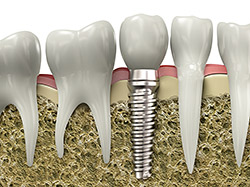

A dental implant is a synthetic tooth root in the shape of a post that is surgically placed into the jawbone. The “root” is usually made of titanium (the same material used in many replacement hips and knees), a metal that is well-suited to pairing with human bone. A replacement tooth is then fixed to the post. The tooth can be either permanently attached or removable. Permanent teeth are more stable and feel more like natural teeth.

implantsImplants are versatile. If you are only missing one tooth, one implant plus one replacement tooth will do the trick. If you are missing several teeth in a row, a few strategically placed implants can support a permanent bridge (a set of replacement teeth). Similarly, if you have lost all of your teeth, a full bridge or full denture can be permanently fixed in your mouth with a strategic number of implants.